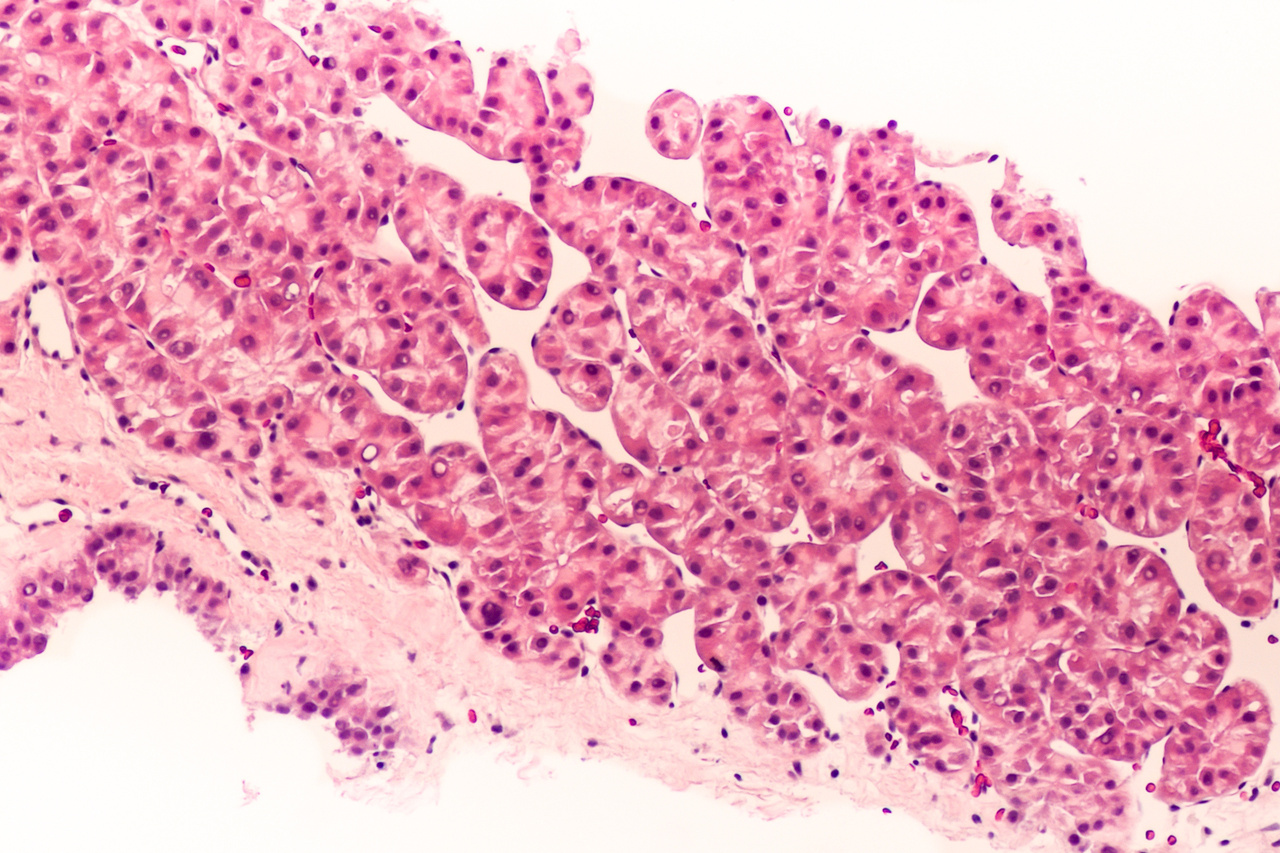

Chez les patients non cirrhotiques, le diagnostic de CHC doit être confirmé par une biopsie hépatique trans­pariétale afin d’obtenir une histologie. Celle-ci joue un rôle essentiel pour éliminer les diagnostics différentiels, déterminer le sous-type de CHC, diag­nostiquer des tumeurs mixtes (CHC et cholangiocarcinome) et évaluer les éléments pronostiques tels que le degré de diffé­ren­ciation, l’invasion microvasculaire et le degré de fibrose du foie sous-jacent. Ainsi, la biopsie hépatique devient de plus en plus l’outil diag­nostique de référence et doit être privilégiée chez la majorité des patients (fig. 2).